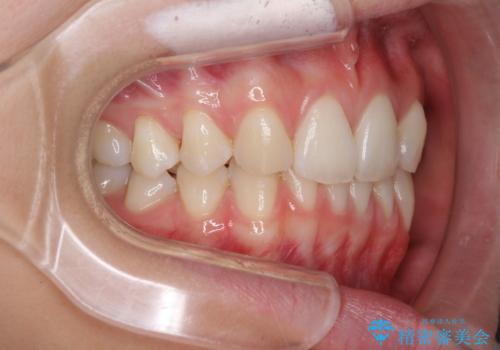

上顎前歯が2本欠損 インビザラインによる叢生の解消

- 深い咬み合わせと前歯のデコボコを気にして来院された患者様です。

上顎前歯2本が欠損しているため、妥協的なゴールを設定しインビザラインで矯正治療を行うこととしました。

上下前歯の大きさのアンバランスにより、深い咬み合わせと奥歯の咬みにくさがなかなか解決されず、治療に長期間を要することとなりました。